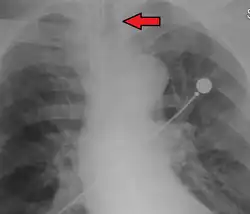

An endotracheal tube in good position on CXR. Arrow marks the tip.

An endotracheal tube not deep enough. Arrow marks the tip.

No single method for confirming tracheal tube placement has been shown to be 100% reliable. Accordingly, the use of multiple methods for confirmation of correct tube placement is now widely considered to be the standard of care.[34] Such methods include direct visualization as the tip of the tube passes through the glottis, or indirect visualization of the tracheal tube within the trachea using a device such as a bronchoscope. With a properly positioned tracheal tube, equal bilateral breath sounds will be heard upon listening to the chest with a stethoscope, and no sound upon listening to the area over the stomach. Equal bilateral rise and fall of the chest wall will be evident with ventilatory excursions. A small amount of water vapor will also be evident within the lumen of the tube with each exhalation and there will be no gastric contents in the tracheal tube at any time.[33]

Ideally, at least one of the methods utilized for confirming tracheal tube placement will be a measuring instrument. Waveform capnography has emerged as the gold standard for the confirmation of tube placement within the trachea. Other methods relying on instruments include the use of a colorimetric end-tidal carbon dioxide detector, a self-inflating esophageal bulb, or an esophageal detection device.[35] The distal tip of a properly positioned tracheal tube will be located in the mid-trachea, roughly 2 cm (1 in) above the bifurcation of the carina; this can be confirmed by chest x-ray. If it is inserted too far into the trachea (beyond the carina), the tip of the tracheal tube is likely to be within the right main bronchus—a situation often referred to as a "right mainstem intubation". In this situation, the left lung may be unable to participate in ventilation, which can lead to decreased oxygen content due to ventilation/perfusion mismatch.[36]